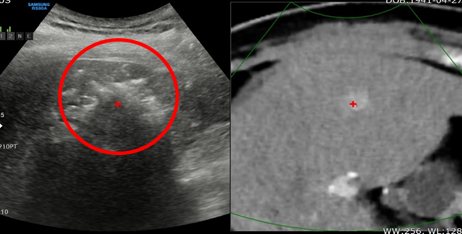

초음파와 CT, MRI 융합기법을 이용하여 고주파 소작치료

치료 전 CT 치료 후 CT